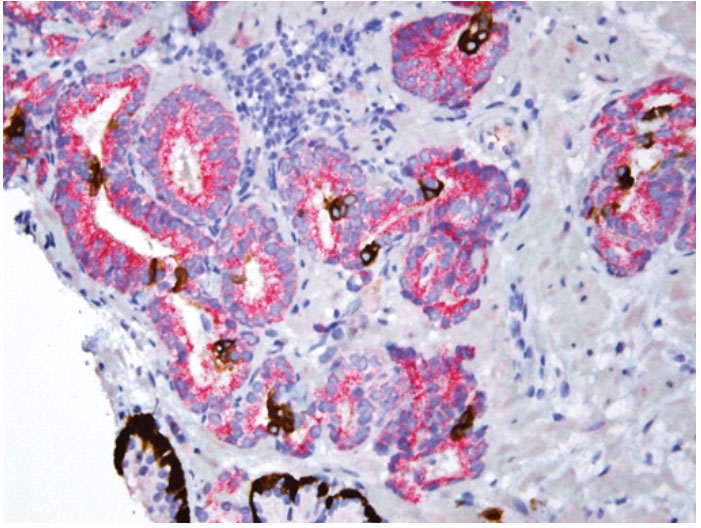

Intraductal carcinoma c dense cribriforming pattern

Same case as left image, showing patchy intact basal layer (p63)

Intraductal Carcinoma of the Prostate (IDC-P)

Intraductal spread of a malignant prostatic AC

- frequently assoc c aggressive and high Gleason score invasive acinar adenocarcinoma

- is a prolif of pleomorphoic malignant cells (with nuclear sizes up to 6x nuclear sizes in adjacent invasive adenocarcinoma)

- expands ductal structures, but has at least a partial / patchy basal cell layer (rules out invasive acinar or ductal AC)

- rarely can be id'd on bx material in absence of infiltrating carcinoma

- vs HG-PIN, has a more dense cribriform pattern with overtly more solid than luminal areas (ie ratio of solid to luminal areas >70%)

- may show small cell-like change

- IDC-P on prostate bx is freq assoc c HG ca and poor px at radical prostatectomy

- thus most likely represents an advanced stage of tumor progression c intraductal spread of tumor in most cases

Infiltrating cribriform acinar AC (Gleason 4 or 5 c comedonecrosis) closely mimics cribriform IDC-P

- most cases if IDC-P would be dx'd as cribriform ca if IHC demonstrating basal cells had not been performed

- in some cases, contour and branching pattern of normal duct architecture suggests the dx of IDC-P as opposed to infiltrating ca

- the tx of IDC-P and infiltrating HG-prostate AC are the same, so distinction not critical on bx

- purely IDC-P at radical prostatectomy is 100% cured by surgery, the same may not be true of an infiltrating ca

- if there is no definitive infiltrating ca on H&E sections and a suggestion of IDC-P in a core, then basal stains are recommended to differentiate IDC-P from infiltrating carcinoma

Intraductal carcinoma of the prostate with PIN4 cocktail highlighting basal cells